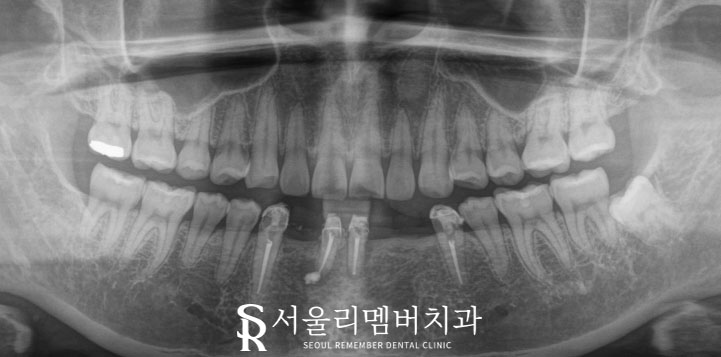

첫 내원 당시 x-ray 사진입니다.

자세히 살펴보면

아랫니가 이미 소실된 채로 오셨는데요,

#43 ~ #34까지 총 7개의 이가 있어야 될 자리에

현재는 4개밖에 남아있지 않았고,

#31,41은 신경치료 후 뿌리 끝에

염증이 생겨있었습니다.